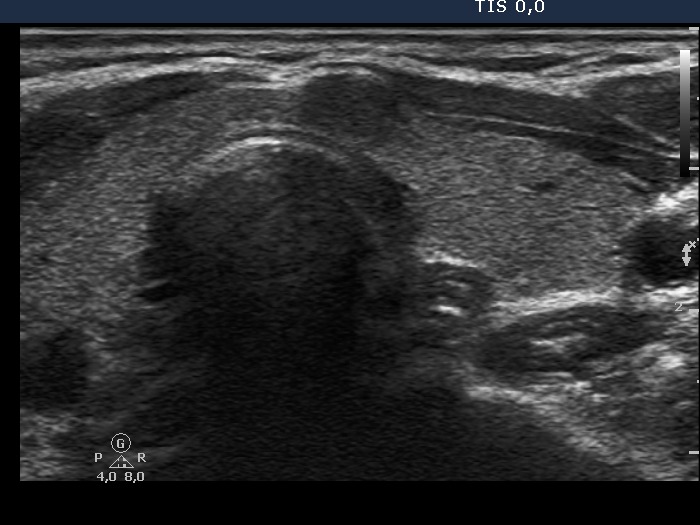

First examination - before surgery (first and second rows of images)

Ultrasonography. The right lobe was echonormal. There was a moderately hypoechogenic, inhomogeneous nodule with blurred borders in the left side of the isthmus. Another cystic nodule was present in the left thyroid.

Cytology of the solid nodule resulted in papillary cancer.